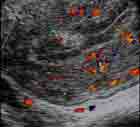

* Au Doppler : Pédicule vasculaire fin et unique.

* Au Doppler : Vascularisation concentrique.